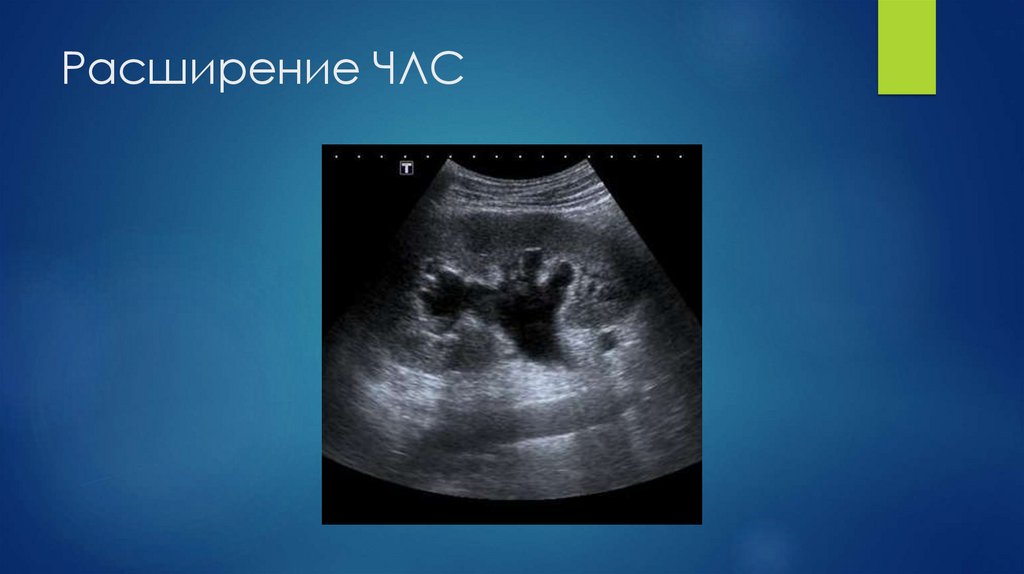

11. Расширение ЧЛС